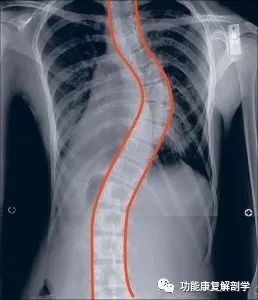

儿童脊柱侧弯的早期识别

治疗脊柱侧弯常常让人感觉像是在和一个比自己领先的对手赛跑。一旦脊柱侧弯的曲度开始发展,父母和医生很容易陷入到应对防止曲度发展的反应当中。